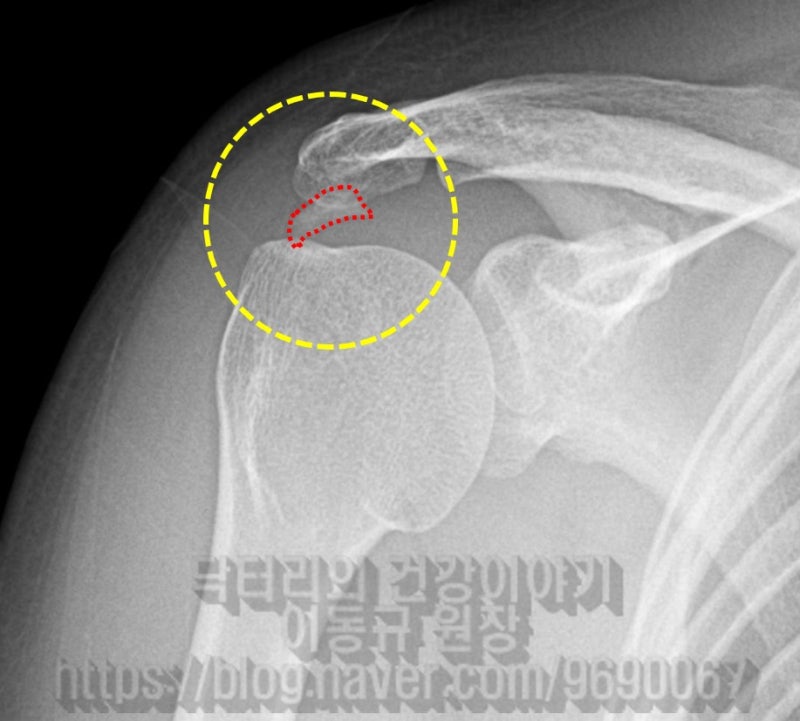

X-ray 사진을 보면 노난 원안에 극상근 부위의 석회성 건염이 보입니다. 빨간 점선으로 표시된 것이 석회입니다.